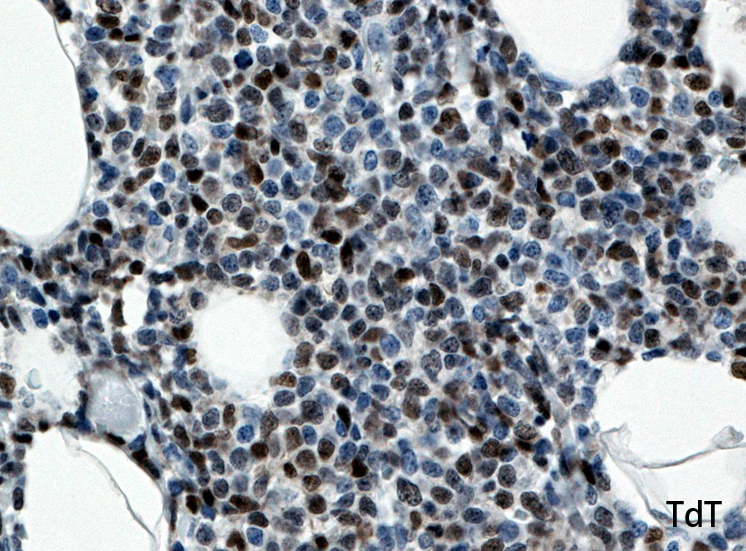

Fig03, Fig04は腫瘍細胞の拡大像。大型異型細胞の出現が認められる。腫瘍細胞はCD4+, CD56+, CD123+

この頃はCD4+, CD56+ にCD123陽性で診断が可能であったが, 他疾患でもこの陽性パターンをとることがわかってきた.